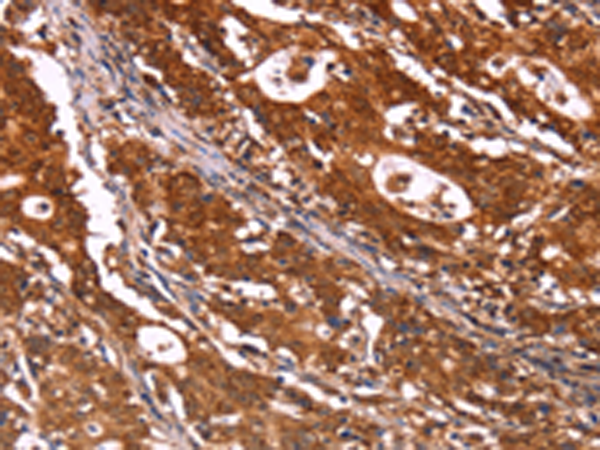

分类: 科研抗体货号: P10641别名: ACEH应用: IHC反应种属: Human, Mouse, Rat